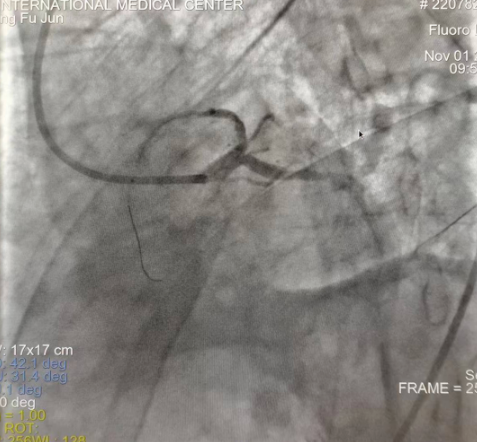

閉塞的血管再通時(shí)間取決于急救時(shí)長、轉(zhuǎn)運(yùn)時(shí)長和治療時(shí)長,在前兩方面,醫(yī)院已為患者爭取了最短時(shí)間?;颊呒覍龠h(yuǎn)在陜北,雖然已在趕來的路上,但最快抵達(dá)西安也要3小時(shí),在與患者家屬電話溝通同意急診手術(shù)后,醫(yī)療總值班代家屬簽字,康曉軍在請示心臟病醫(yī)院王海昌院長及心臟內(nèi)科CCU尚福軍主任后,積極進(jìn)行術(shù)前準(zhǔn)備。在沒有家屬陪同、沒有交費(fèi)、沒有辦入院手續(xù)的情況下,患者經(jīng)胸痛中心綠色通道被送往心臟冠脈介入手術(shù)室,打通了完全閉塞的心臟前降支近段血管。